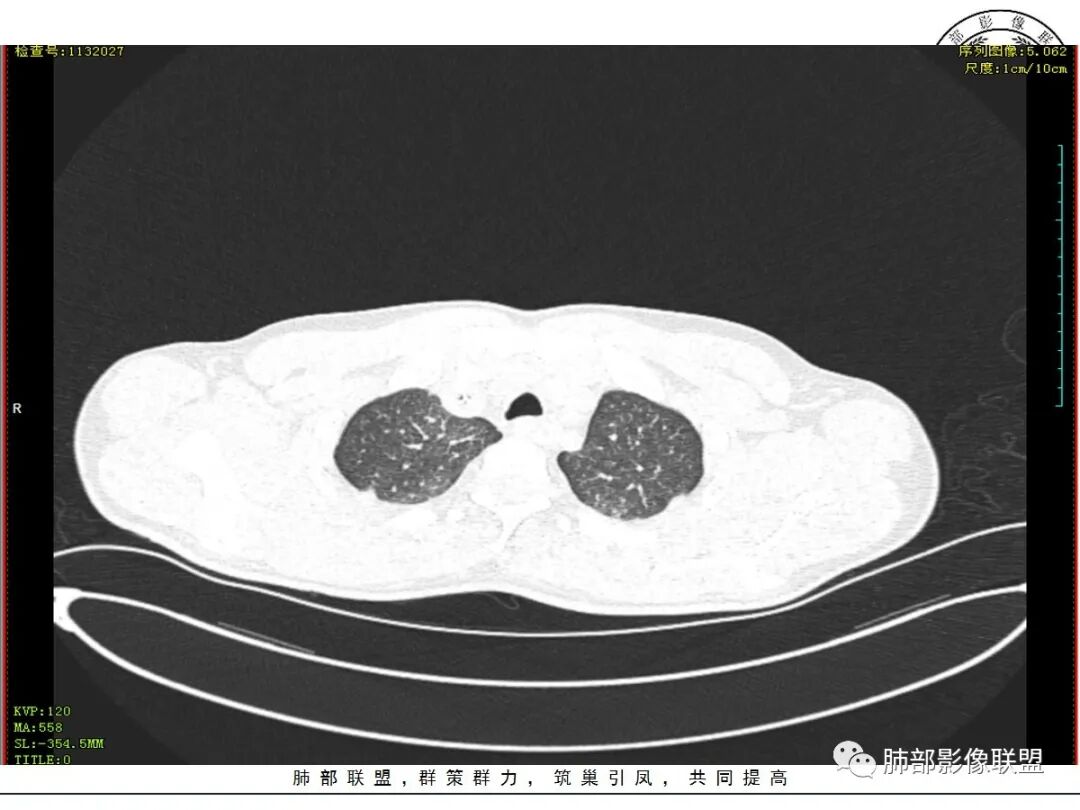

青年男性患者,气促7小时入院,白细胞及中性粒明显增高,PCT增高,CRP不高,心率快,呼吸急促,意识模糊,低氧血症,I型呼吸衰竭,PH偏低,失代偿性酸中毒,BNP偏高,胸部CT:双肺弥漫性多发斑片状实变密度影,双上肺明显,间质改变为主,综合:年轻男性,急性起病,迅速恶化,考虑中毒可能,鉴别:PCP,过敏,

双肺上叶,下叶背段多发斑片状实变影,以胸膜下分布为主,部分重力作用,以背侧为主,部分小叶间质增厚,部分周围伴有散在磨玻璃影,边界欠清,临床急性病程,血象增及PCT明显增高,意识模糊,考虑:吸入性肺炎?鉴别:AHP?CEP?PCP

37岁男性 气促 两肺对称分布磨玻璃及小叶间隔增厚,两肺上叶后段及下叶背段为著,有重力分布,下部密度较高,请结合病史排查肺水肿,理化性肺泡损伤

双肺叶透亮度对称性减低,呈磨砂状,小叶间隔规则增厚,上叶为甚,左右肺叶中轴间质增厚(示淋巴回流障碍),双肺叶弥散磨GGO征,以肺腺泡分布,双肺上,下叶融合片状,有重力分布特点,心脏大,肺动脉干增粗,首选心源性肺水肿,但无胸腔积液。与急性肺损伤和ARDS鉴别

影像:两肺上叶小叶间隔增厚,斑片,腺泡结节,重力分布,下肺不累及

双肺弥漫性病变以上肺,向心性,背部分布为主,肺动脉干无增粗,急性起病,典型的吸入性肺炎。

青年男性,气促7小时入院,意识模糊,白细胞及中性粒明显增高,PCT增高,CRP不高,心率快,体温正常,血压正常。胸部CT:双肺上叶小叶间隔光滑增厚,中轴间质增厚,弥漫性磨玻璃、多发斑片影,以上肺、背侧分布为主。影像表现考虑为肺水肿。病因:病史不支持肾功能衰竭、心源性、高原性肺水肿,无发热,似乎也不支持细菌、病毒、真菌等感染引起。吸入毒物?吸入水?

病灶的分布以上肺为主

确实要考虑吸入,倾向于吸入的是气体类的可能,因为朝上走

结合病史,最终诊断是 “急性烟雾吸入性肺损伤”,影像学表现主要是肺水肿及弥漫性肺泡损伤改变,因为烟雾气体吸入肺内分布以上肺显著,因此影像学表现也是累及上肺更明显。损伤因素包括大量一氧化碳 二氧化碳 一氧化氮等燃烧产生的有毒气体,也有烟雾粉尘颗粒对气道黏膜的损伤。